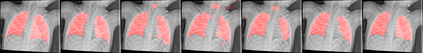

UNet and its variants have been widely used in medical image segmentation. However, these models, especially those based on Transformer architectures, pose challenges due to their large number of parameters and computational loads, making them unsuitable for mobile health applications. Recently, State Space Models (SSMs), exemplified by Mamba, have emerged as competitive alternatives to CNN and Transformer architectures. Building upon this, we employ Mamba as a lightweight substitute for CNN and Transformer within UNet, aiming at tackling challenges stemming from computational resource limitations in real medical settings. To this end, we introduce the Lightweight Mamba UNet (LightM-UNet) that integrates Mamba and UNet in a lightweight framework. Specifically, LightM-UNet leverages the Residual Vision Mamba Layer in a pure Mamba fashion to extract deep semantic features and model long-range spatial dependencies, with linear computational complexity. Extensive experiments conducted on two real-world 2D/3D datasets demonstrate that LightM-UNet surpasses existing state-of-the-art literature. Notably, when compared to the renowned nnU-Net, LightM-UNet achieves superior segmentation performance while drastically reducing parameter and computation costs by 116x and 21x, respectively. This highlights the potential of Mamba in facilitating model lightweighting. Our code implementation is publicly available at https://github.com/MrBlankness/LightM-UNet.